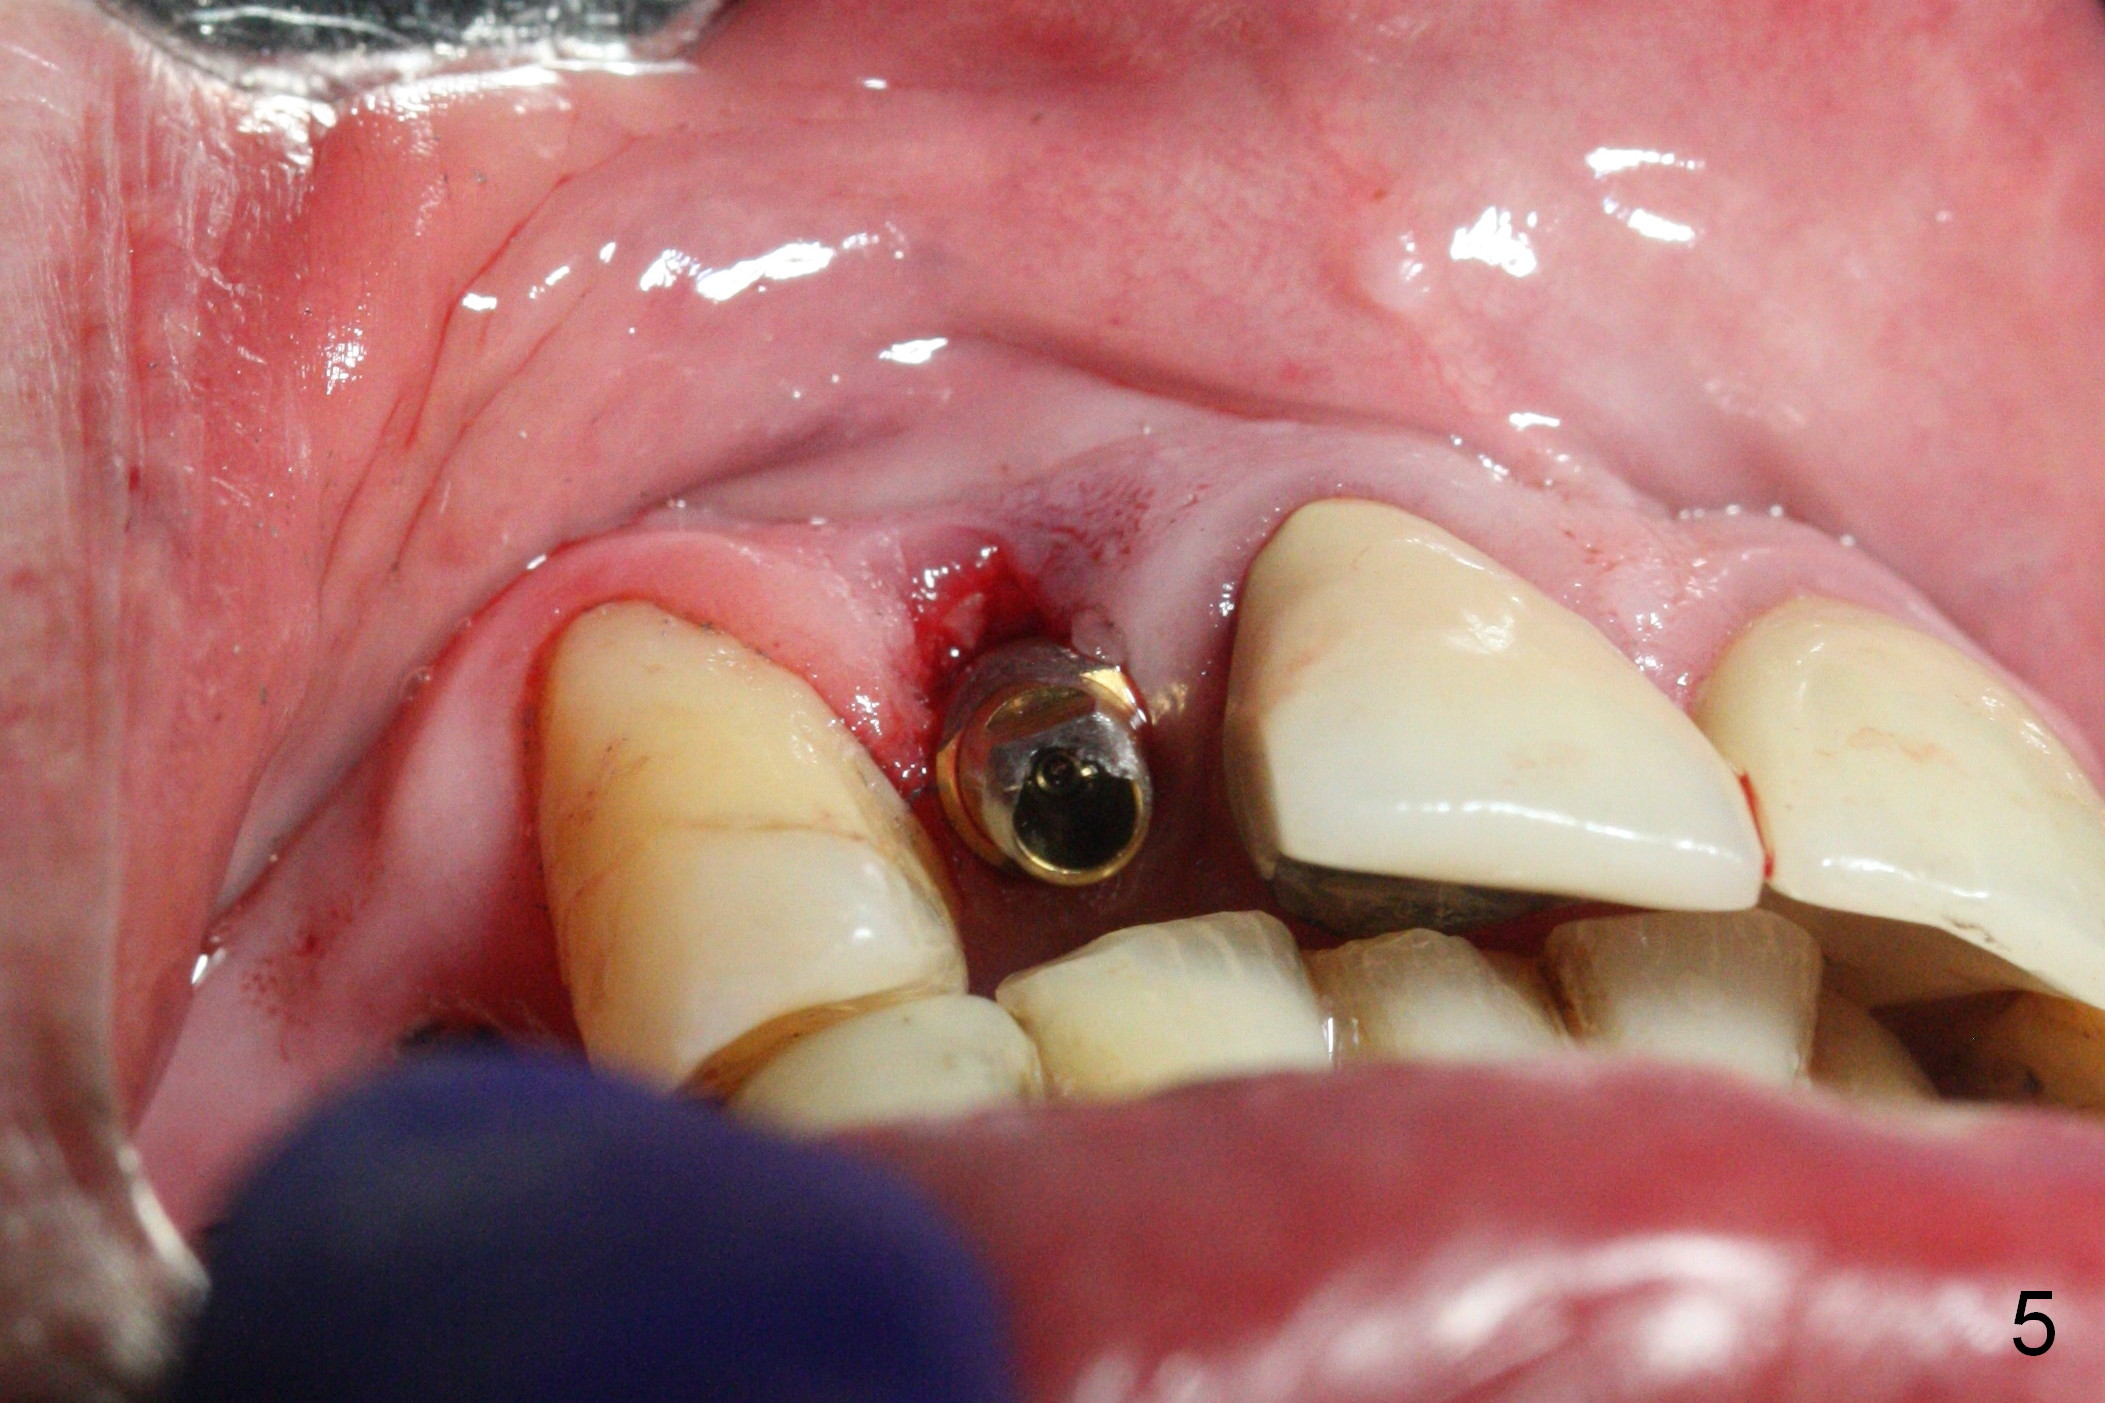

The residual root at #7 is fairly well exposed with buccal gingival recession (Fig.1). The implant placement is flapless (Fig.2-7). What is not shown is that the 3.8x13 mm implant is buccally subcrestally placed (Fig.3). After 1st round of bone graft buccal to the implant, a 4.5x5(5) mm abutment is immediately placed and prepared (Fig.4,5). An immediate provisional is placed after 2nd round of bone graft subgingivally buccally (Fig.6,7). Note the bulging gingiva (*), as compared to that in Fig.4,5. The long implant is chosen because of anterior deep bite (Fig.4) and lack of posterior support (Fig.7).